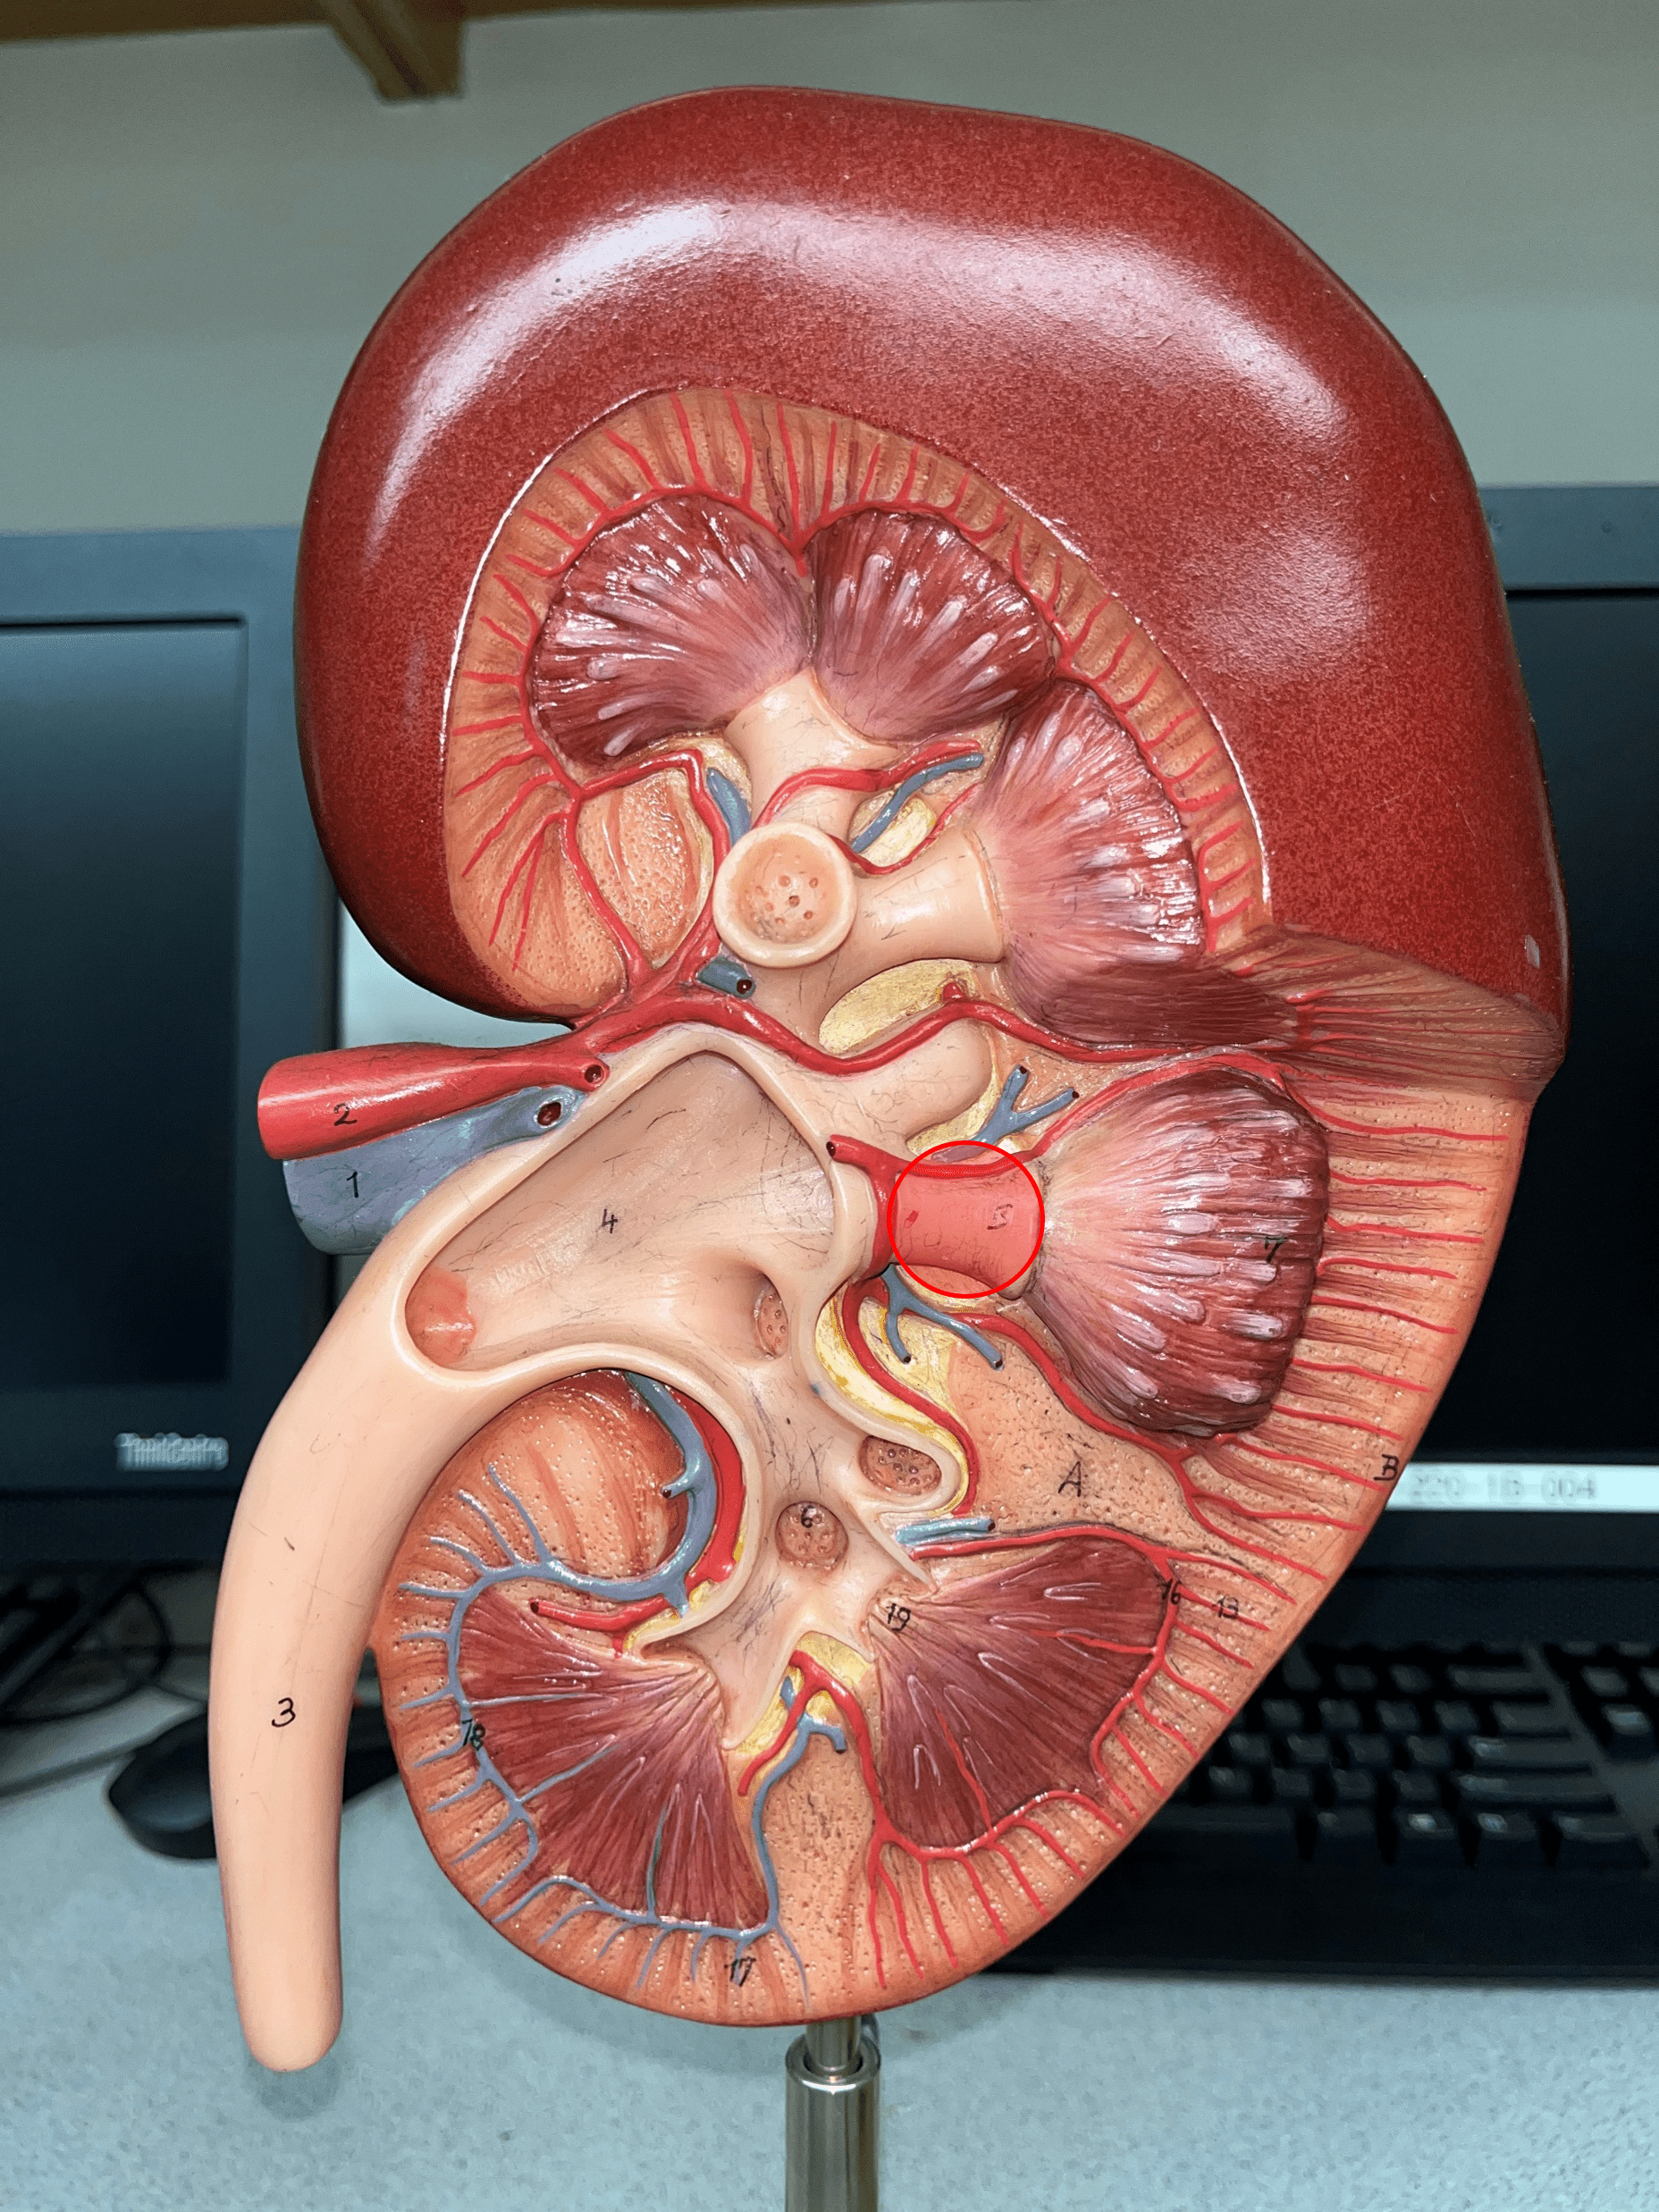

segmental artery

• Branches of the renal a.

• Branches into smaller interlobar aa.

• Branches into smaller interlobar aa.